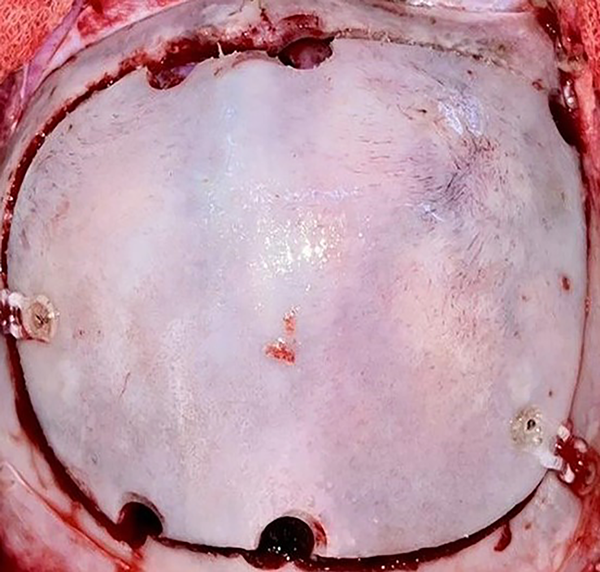

Se colocó al paciente en posición supina con la cabeza levemente deflexionada, utilizando un cabezal en herradura (Figuras 4 y 5). Luego de la infiltración local anestésica de la zona, se realizó una incisión bicoronal en zigzag, respetando la arteria temporal superficial. Se procedió con la disección subgaleal y se rebatió el colgajo cutáneo. Se hizo una craneotomía frontal amplia de 8 x 5 cm con drill de alta velocidad y se expuso la duramadre subyacente (Figura 6).

Figura 6. Agujeros de trépano parasagitales para realizar plaqueta ósea.